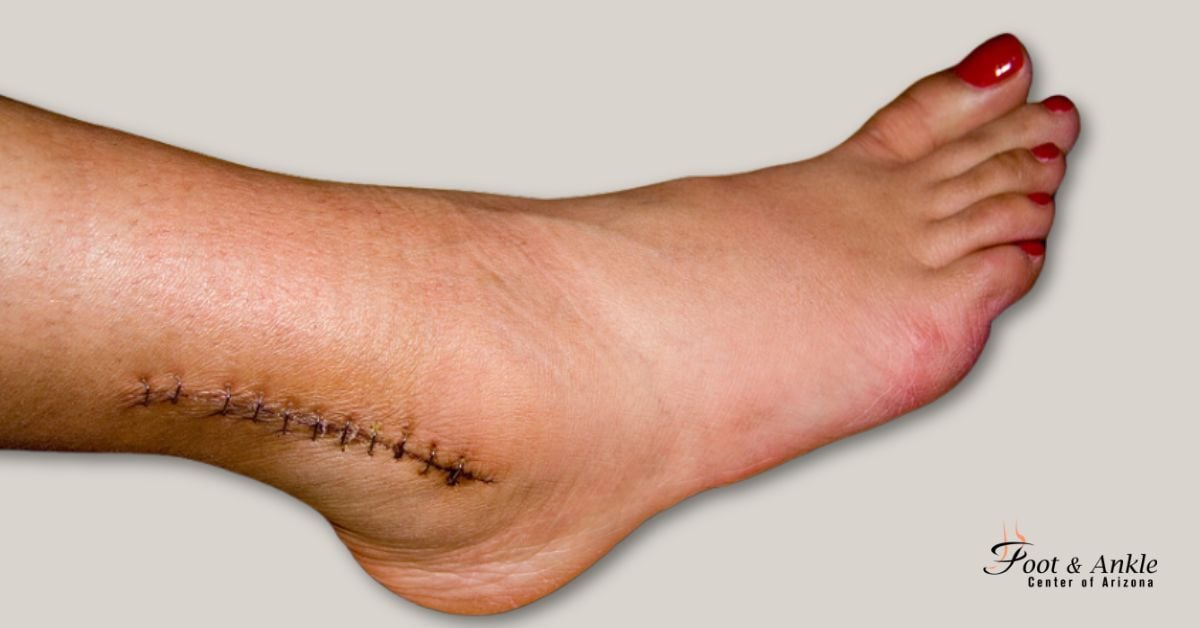

When is needed to treat your ankle injury, the Foot and Ankle Center of Arizona provides you with the finest foot and ankle care to get you back on your feet, using only the highest quality equipment and provides the leading surgical techniques to help you find relief.